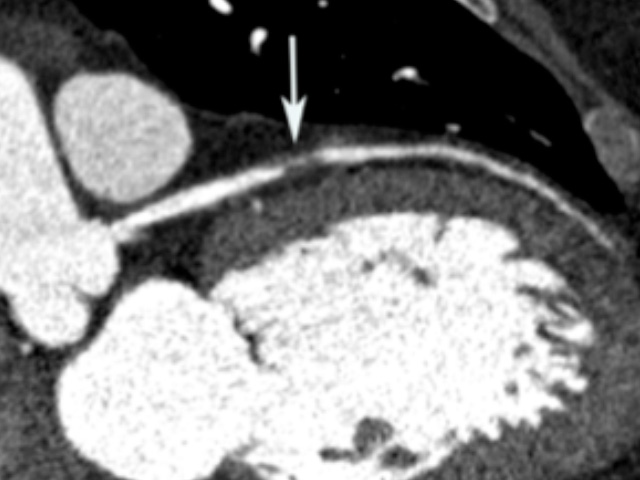

Coronary CT demonstrating severe stenosis of the left anterior descending coronary artery (arrow).

Our recently completed multicenter randomized controlled trials have established the efficacy of a coronary CT angiography-based diagnostic strategy for chest pain. The ROMICAT II trial (n=1,000) found that a CT for acute chest pain resulted in improved efficiency of clinical decision making. The PROMISE trial (n=10,000) found that a CT diagnostic strategy resulted in similar outcomes to functional testing for stable chest pain. Our current efforts focus on whether coronary plaque morphology can predict which patients are at greatest risk.